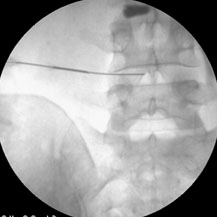

Ozone neucleolysis or ozone discectomy is a non-operative intervention for slipped disc / disc prolapse & discogenic pain. Ozone discectomy is a day care procedure and general anaesthesia is not required. Total cost of the procedure is much less and is very safe compared to other procedures. It has been implicated as one of the important cause of low back pain radiating to limbs. Apart from conservative therapy all other forms of treatment aim at decompressing the nerve roots. These can be done by taking the disc out by surgery or by decompressing the foremen and disc by different interventions. The various treatment options have confused clinicians due to significant failure rate associated with different kinds of surgeries as well as with different interventions.

Epidural steroid injection, transformational epidural decompressions has a high success rate (up to 85%) but chances of recurrences are there specially if these interventions are done at later stage. Chemonucleolysis using chymopa pain has also high success rate (80%) with low recurrences but not popular owing to the chances of anaphylaxis following intradiscal chymopa pain injection. Injection of ozone for discogenic radiculopathy (low back pain with radiation to legs) has developed as an alternative to chemonucleolysis and disc surgery owing to its high success rate, less invasiveness, fewer chances of recurrences and remarkably fewer side effects.

The action of ozone is due to the active oxygen atom liberated from breaking down of ozone molecule. When ozone is injected into the disc the active oxygen atom called the singlet oxygen or the free radicle attaches with the proteo-glycan bridges in the jelly-like material or nucleus pulposus. They are broken down and they no longer capable of holding water. As a result disc shrinks and mummified and there is decompression of nerve roots. It is almost equivalent to surgical discectomy and so the procedure is called ozone discectomy or ozonucleolysis. Besides, it has an anti-inflammatory action due to inhibitions of formation of inflammation producing substances and tissue oxygenation is increased due to increased 2,3 diphosphoglycerate level in the red blood cells. All these leads to decompression of nerve roots, decreased inflammation of nerve roots, increased oxygenation to the diseased tissue for repair work.

Ozone nucleolysis or ozone discectomy has a success rate of about 80%. On the other hand surgical discectomy has much higher side effects compared to remarkably few side effects of ozone discectomy. Ozone discectomy is usually a day care procedure and general anaesthesia is not usually required. Total cost of the procedure is much less than that of surgical discectomy. All these facts have made this procedure very popular at European countries. It is also gaining popularity in our country due to low cost, less hospital stay, no post-operative discomfort and morbidity and very few side effects.